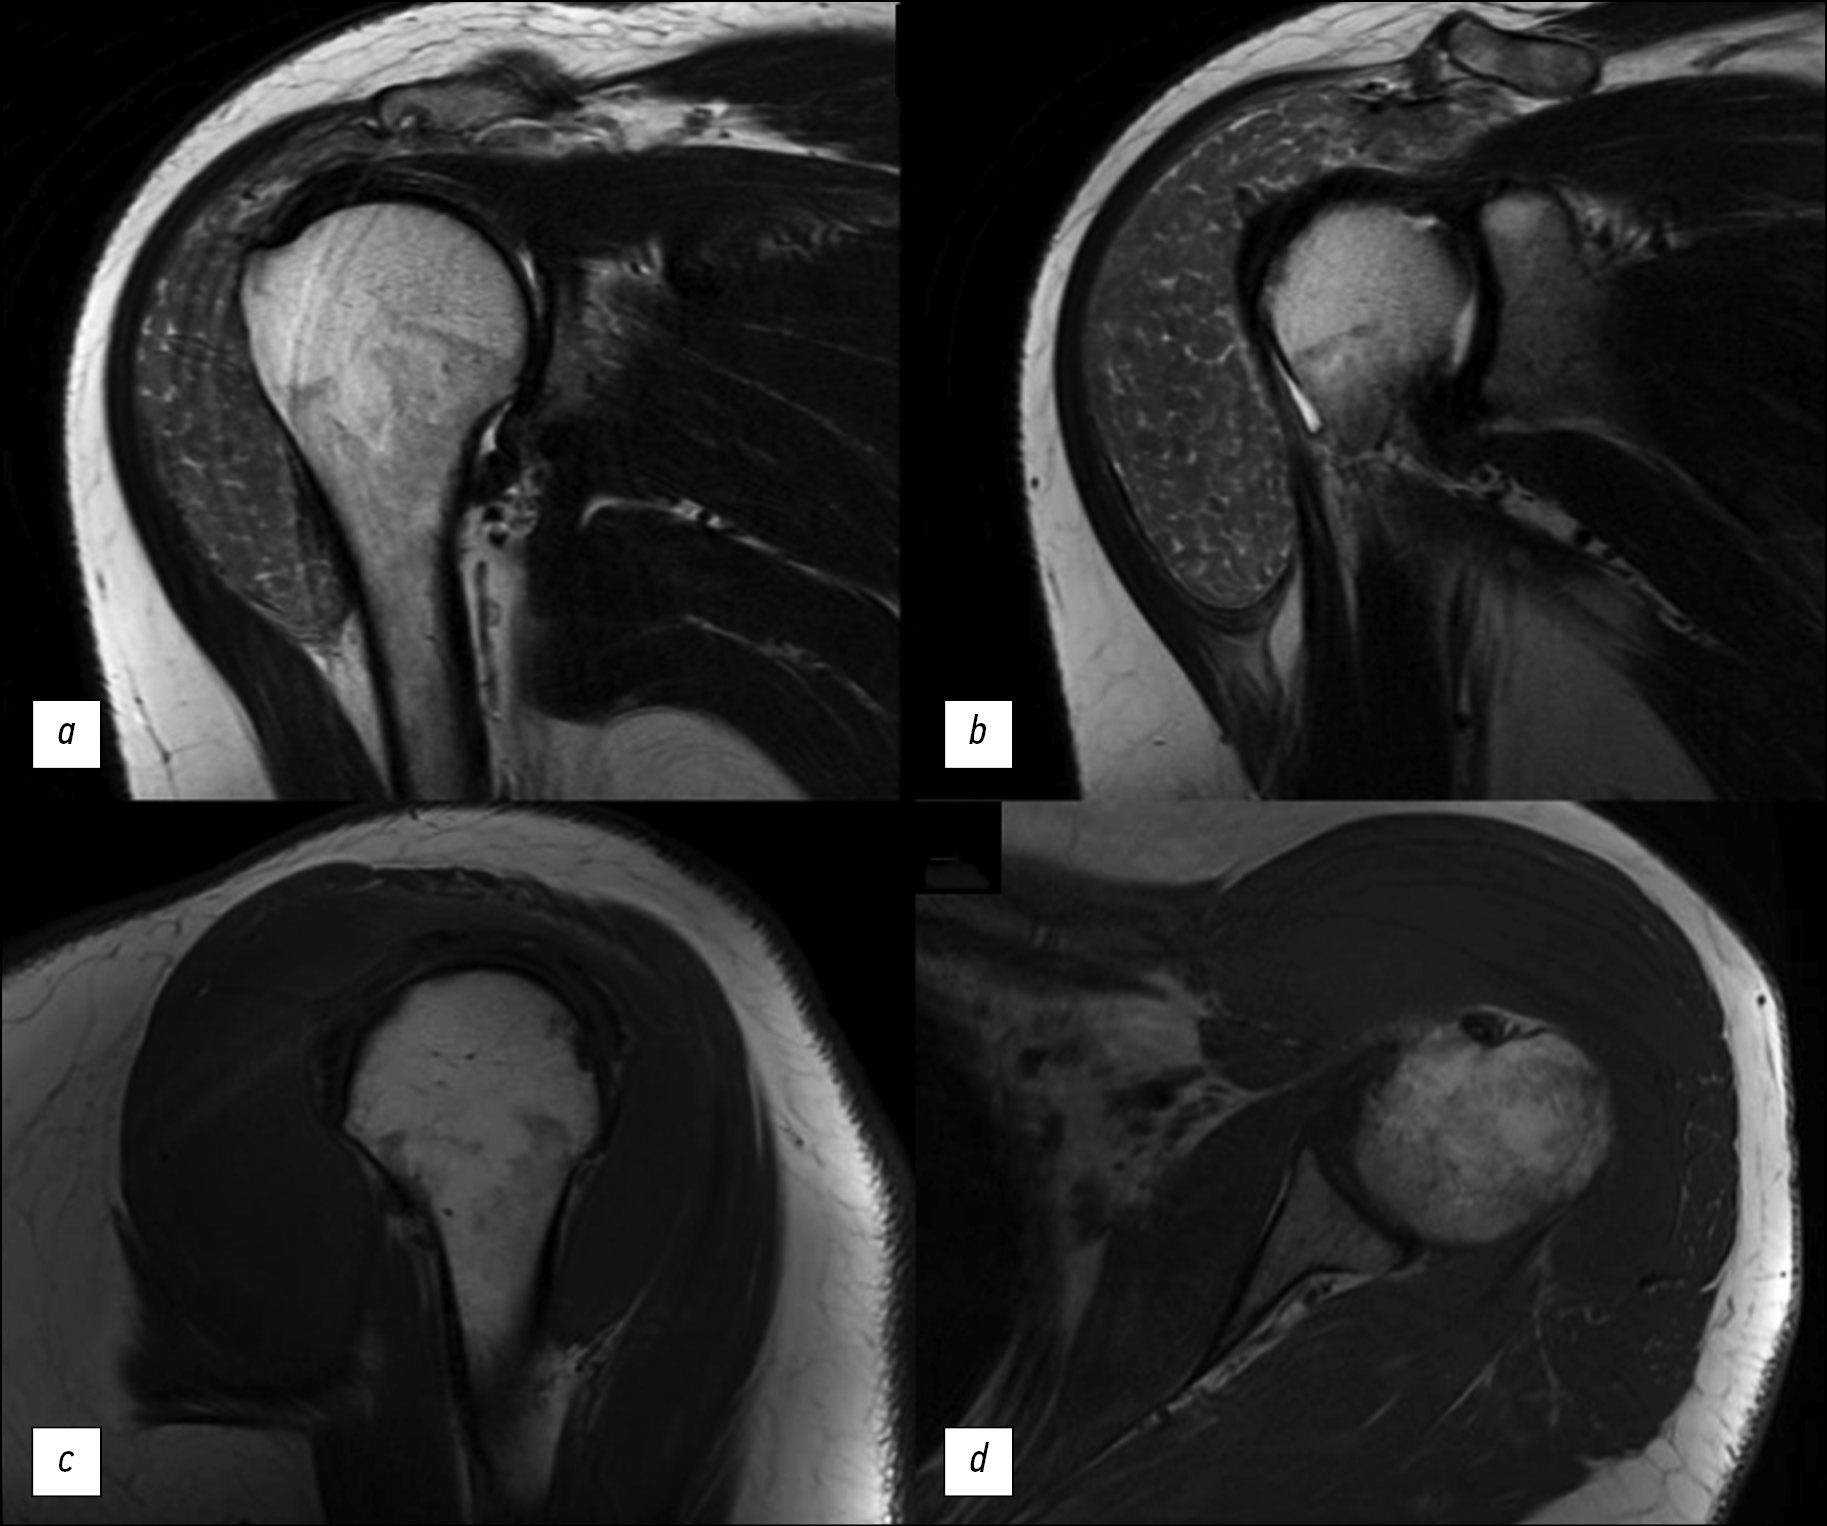

The “rice bodies” symptom on magnetic resonance imaging of the shoulder joint in patients with rheumatoid arthritis is a rare but specific finding characterized by the presence of multiple small, round, rice-grain-like structures in the synovial fluid of the joint, synovial pouches, or sheaths. The etiology of the “rice bodies” is still not fully understood. They are suggested as the result of microinfarcts of the synovial membrane in patients with rheumatoid arthritis or other inflammatory joint diseases. Clinically, the “rice bodies” symptom may cause pain, but not in every case. Among radiological diagnostic methods, magnetic resonance imaging is the leading method for the detection of rice bodies. This article presents a clinical case of “rice bodies” symptoms diagnosed by magnetic resonance imaging in a patient with a long history of rheumatoid arthritis who presented with a painless enlargement in the left shoulder. Computed tomography and magnetic resonance imaging of the left shoulder could detect “rice bodies” as a manifestation of an underlying disease and determine further treatment techniques.